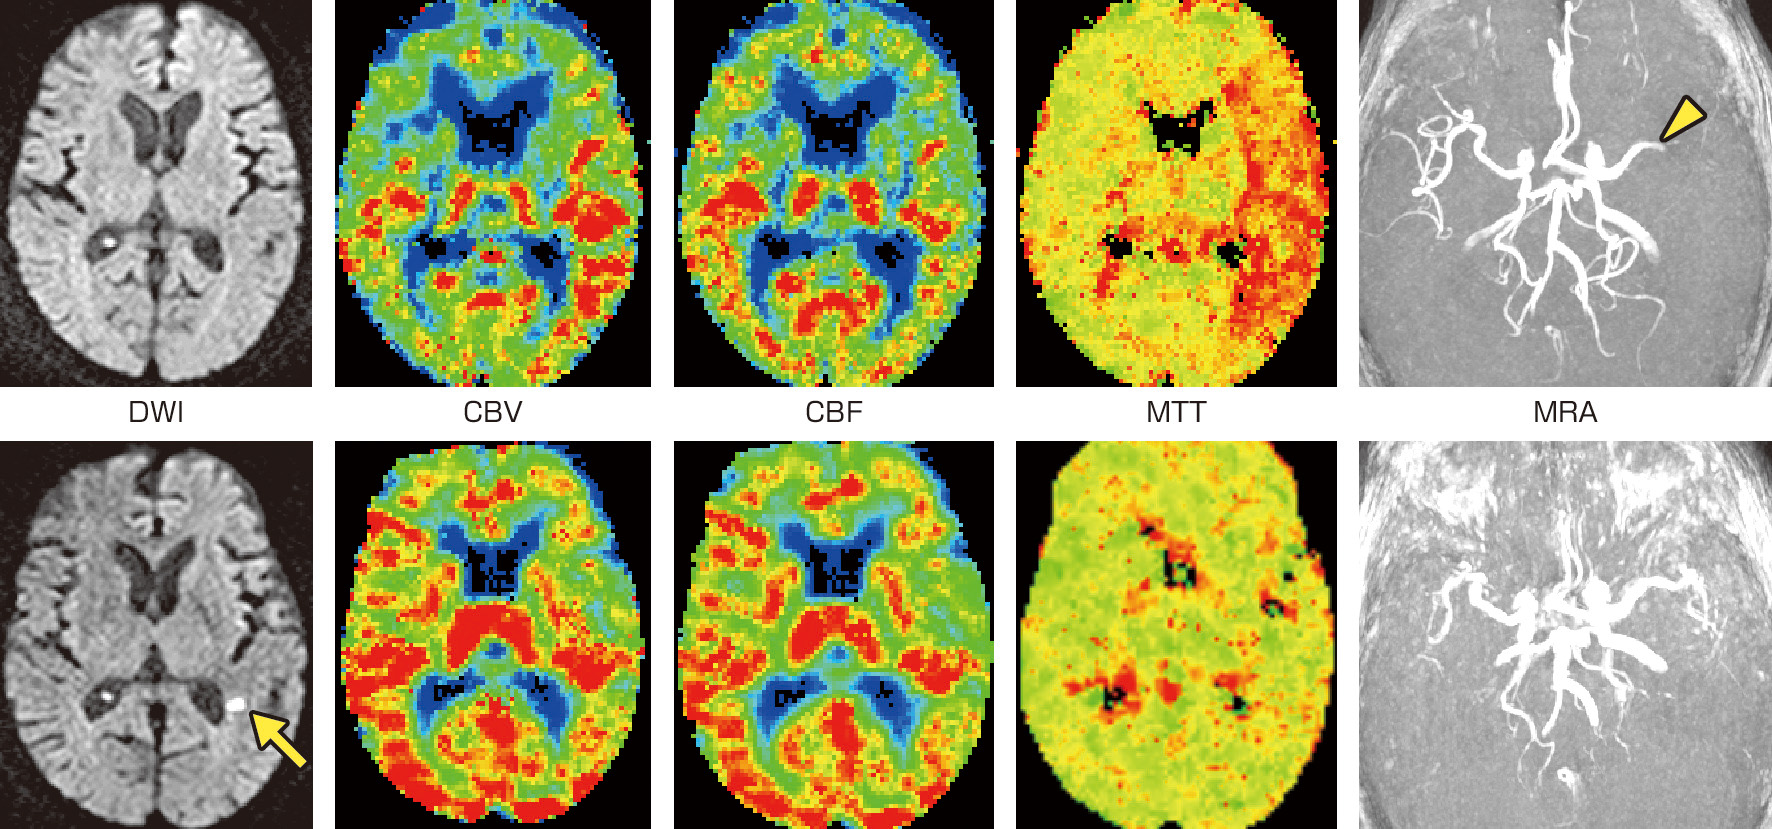

ⓔ図18-4-18 超急性期脳梗塞のMRI 70歳代,女性.発症2時間後 (上段),および8日後 (下段) のMRIを示す.初回検査ではMRAにて左中大脳動脈の途絶がみられる (矢頭).拡散強調画像 (DWI) で急性期脳梗塞は指摘できない.一方,灌流画像では左中大脳動脈領域における平均通過時間 (mean transit time: MTT) の延長が観察される.このような所見上の解離をdiffusion–perfusion mismatchとよぶ.血栓融解療法を行った後に施行された追跡検査 (下段) ではMTTの左右差が解消している.拡散強調画像では脳室周囲の白質に1カ所,小さな高信号を認め急性期脳梗塞を反映している.灌流異常が存在した領域の大半が脳梗塞に至らずに済んだことになる. CBV: cerebral blood volume,CBF: cerebral blood flow.